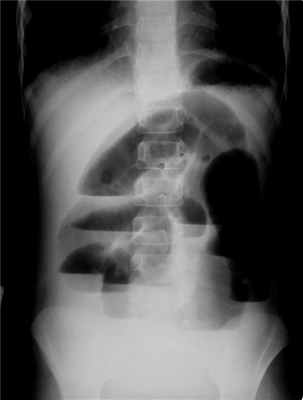

Главным рентгенологическим симптомом острой кишечной непроходимости является появление чаш Клойберга — горизонтальных уровней и куполообразных участков просветления (газов) над ними. Окончательный диагноз устанавливают во время лапаротомии.

Диагностика сарком тонкой кишки основывается на клинической картине, пальпации опухоли в брюшной полости и данных, обнаруженных во время рентгенологического исследования тонкой кишки (пассаж бария сульфата). Для опухолей, которые растут вне просвета кишки, характерен краевой дефект наполнения или большое депо контрастной массы, вызванное распадом опухоли.

При наличии сарком, которые растут в просвет кишки, наблюдается дефект наполнения, обрыв складок слизистой оболочки, супрастенотическое расширение кишки.

Диагностика рака тонкой кишки сложна и базируется на результатах рентгенологического исследования. Рентгенологически определяют признаки сужения просвета тонкой кишки, которые характеризуются длительной задержкой контрастного вещества в двенадцатиперстной кишке, расширением петли над местом сужения. Сонографически обнаруживают распространение опухоли на смежные структуры, наличие метастатического поражения. Значительную помощь в диагностике рака тонкой кишки, его распространения на соседние анатомические образования оказывает компьютерная томография. Очевидно, с внедрением в практику фиброволоконной оптики, что позволяет проводить тотальную еюноилеоскопию, диагностика этих заболеваний в ближайшие годы значительно улучшится.